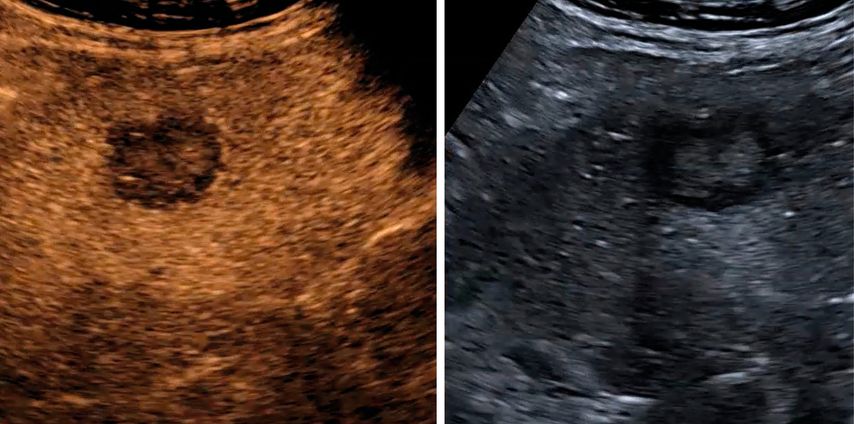

In der früharteriellen Phase zeigen benigne Läsionen wie Hämangiome typische Füllungsmuster ohne «wash-out» in der Portal- oder Spätphase (Abb.1). Maligne Läsionen hingegen weisen meist ein rasches «wash-out» auf und stellen sich in der Spätphase hypokontrastiert dar (Abb.2).3,4

Abb. 2: Darstellung einer hochgradig Metastasen-suspekten Raumforderung bei Mamma-Neoplasie im linken Leberlappen im B-Bild-Modus (rechts) sowie in der Spätphase nach Gabe von 1,6 ml SonoVue® mit Darstellung eines deutlichen «Wash-out»-Phänomens in der Spätphase 4 Minuten nach Injektion des Kontrastmittels (links)